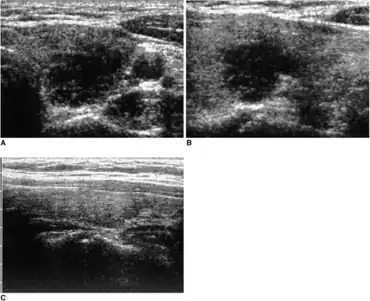

Diagnosis

With the standard overactive thyroid, iodine uptake into the thyroid is avid, whereas if the cells are damaged, then uptake is poor. In this way, if there is doubt about whether the patient has too much thyroid hormone because of de Quervain's thyroiditis, then measuring radio-iodine uptake or technetium uptake gives a clear cut answer as it will be higher than normal in standard thyrotoxicosis and lower than normal in de Quervain's.